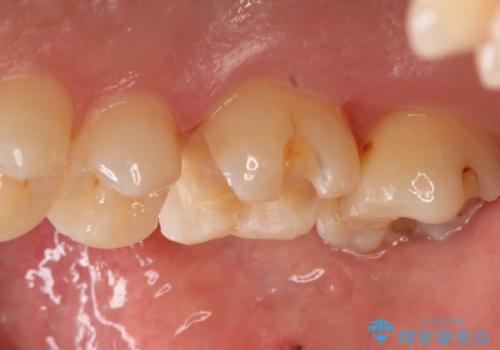

- 右上6番の銀歯をセラミックに変えたいと希望された患者様です。

切削量、形態を考慮し、セラミックインレーでの治療を計画しました。

銀歯と虫歯を除去した上でCRで裏層し形態を整えて印象を行っています。